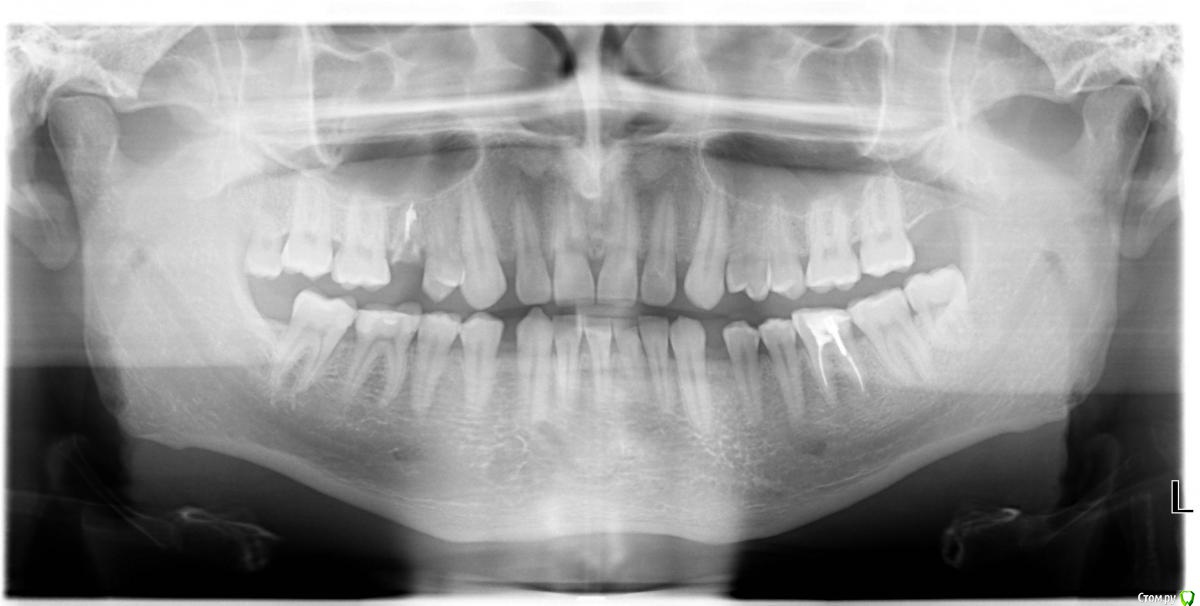

akudja Опубликовано 11 января, 2017 Поделиться Опубликовано 11 января, 2017 (изменено) Доброго времени суток.Интересует другое мнение по ситуации с зубами, есть три ортопантомограммы сделанные в разный промежуток времени:04.04.2014 14.06.2016 11.01.2017 1. Кто либо видит где нибудь кисту по этим снимкам?2. Действительно ли каналы 36го зуба (правый нижний ряд по снимку, 6ой зуб) недопломбирован/ы?3. Наиболее оптимальное решение для указанного в вопросе № 2 зуба - доделка и установка коронки или удаление с последующей имплантацией?4. 18й зуб (левый верхний ряд, последний зуб) есть ли необходимость в его удалении при условии, что он здоров, соседние зубы не трогает и им не мешает, владельцу зуба также никаких неудобств не доставляет? Так как будучи пациентом удостовериться в достоверности диагноза врача нет возможности, остается уповать на его добросовестность, но хотелось бы иметь разностороннюю точку зрения. Заранее благодарю за ответы. Изменено 11 января, 2017 пользователем akudja Ссылка на комментарий

red_butler Опубликовано 12 января, 2017 Поделиться Опубликовано 12 января, 2017 1. Кто либо видит где нибудь кисту по этим снимкам? для постановки данного диагноза требуется гистологическое исследование. 2. Действительно ли каналы 36го зуба (правый нижний ряд по снимку, 6ой зуб) недопломбирован/ы? да 3. Наиболее оптимальное решение для указанного в вопросе № 2 зуба - доделка и установка коронки или удаление с последующей имплантацией? Для ответа нужен очный осмотр 4. 18й зуб (левый верхний ряд, последний зуб) есть ли необходимость в его удалении при условии, что он здоров, соседние зубы не трогает и им не мешает, владельцу зуба также никаких неудобств не доставляет? удаляйте, зуб лишен антагониста, выдвинулся и поражен кариесом. 1 Ссылка на комментарий